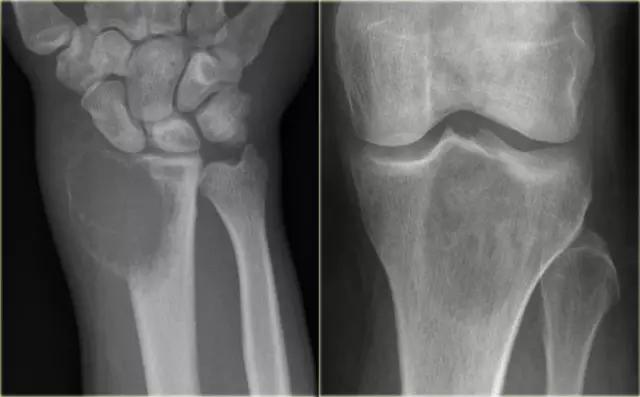

在左图,桡骨的一个骨巨细胞瘤具有不明确的边缘,破坏软骨下骨板和向软组织延伸。在右图,在胫骨近端的巨细胞瘤具有稍微更好的限定的边缘和非中断的皮质骨。

注意侵袭性外观与不明确的边界,延伸到软组织和软骨下骨板的破坏。

在骨骺和干骺端的定位有利于GCT的诊断。在右侧冠状T1加权CE图像。

有弥漫性不均匀强化,并延伸至腕关节和骨和软组织周围水肿。